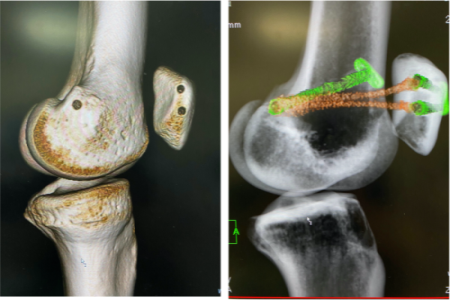

膝蓋骨脱臼

手術:我々は、膝蓋骨の内側支持機構である内側膝蓋大腿靱帯(Medial patellofemoral ligament; MPFL)再建術を第一選択としております。膝蓋骨と大腿骨のMPFLの付着している位置に性格に骨孔を作成し、ネジやボタンにて上記の腱を固定します。症例によっては外側支帯解離術・骨切り術が必要となる場合がございます。成績をおさめています。